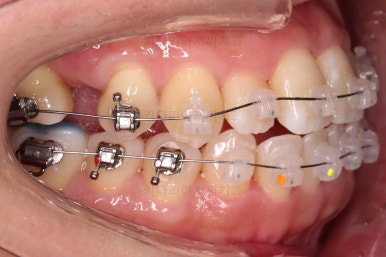

아랫니는 중앙선을 맞추기 위해서 미니스크류를 이용해 한 쪽으로 당기는 중이고요.

이 과정에서 아랫니들이 약간은 뒤로 들어가져서 아랫입술 부위의 돌출감을 아주 약간은 줄일 수 있습니다.

윗니 임플란트 할 자리는 적절히 계속 맞춰줍니다.

중앙선도 점점 맞아지고 있어요.

임플란트 할 공간도 여유롭게 마련이 되었네요.